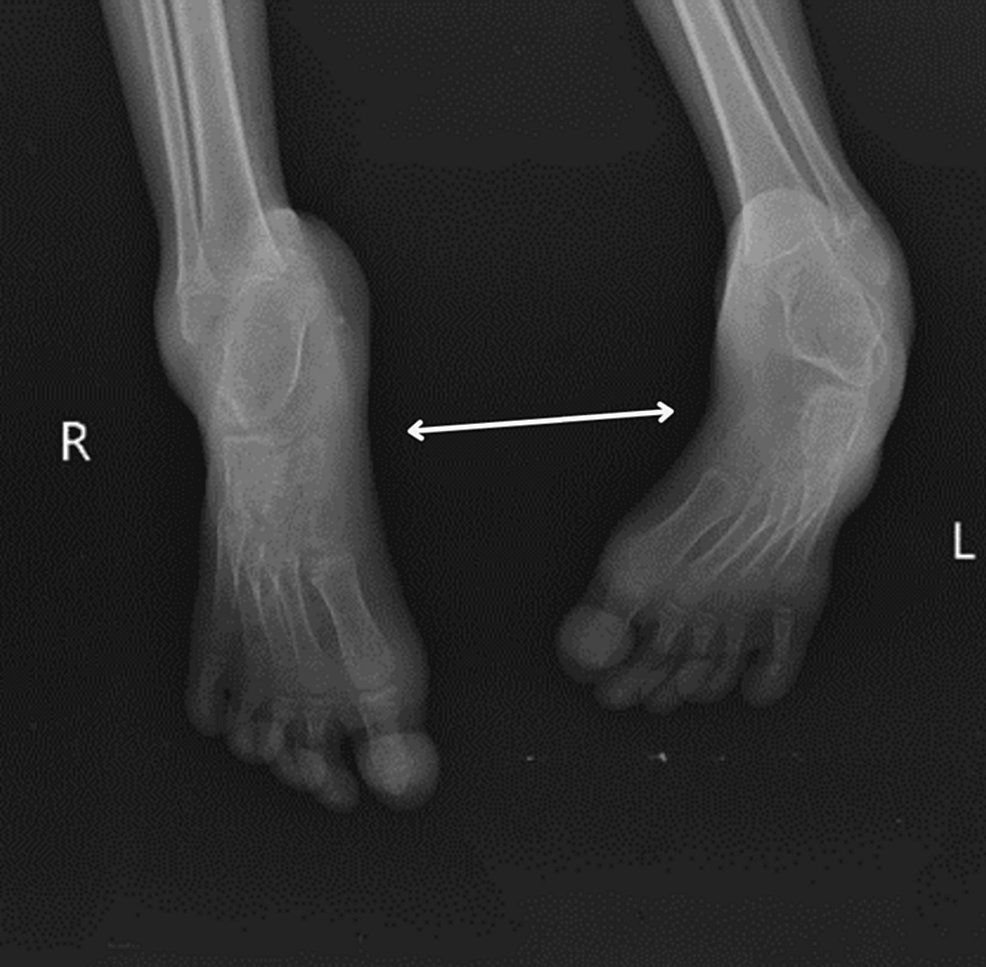

Treatment of talipes equinovarus after triceps surae intramuscular

From www.wjgnet.com

Treatment of talipes equinovarus after triceps surae intramuscular Talipes Equinovarus Physiotherapy Treatment this guideline covers the primary diagnosis and treatment of idiopathic clubfoot in children presenting with the deformity in the first 6. Identify interprofessional team strategies for improving. when you look at their foot, the bottom often faces sideways or even up. Another name for club foot is talipes equinovarus. Stretching and casting (ponseti method) surgery. treatment options. Talipes Equinovarus Physiotherapy Treatment.